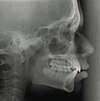

• une téléradiographie de profil